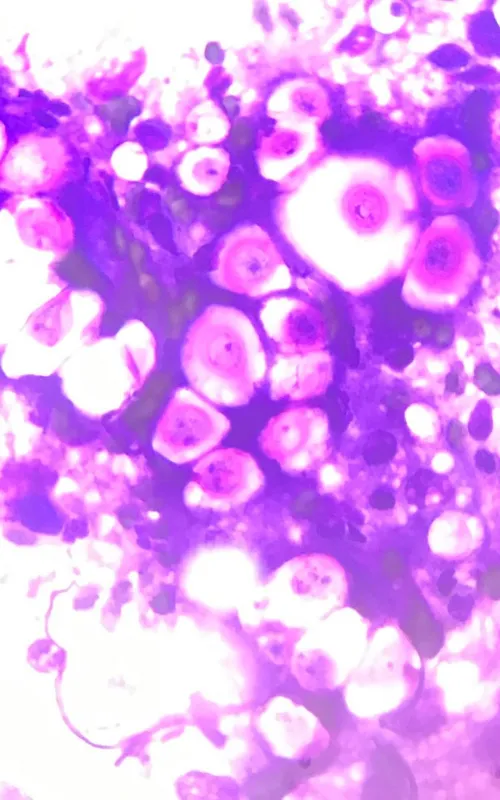

Lando first saw his local vet in May 2023 after a firm swelling appeared under his chin. A fine needle aspirate showed significant pyogranulomatous inflammation and numerous yeast forms consistent with Cryptococcus species.

Under the care of Dr Wan Ju Jao, Lando had surgery to remove the affected lymph node and reduce the fungal burden. Testing of the tissue confirmed severe lymphadenitis caused by cryptococcosis, and a serum cryptococcal antigen test showed high levels. Analysis of his cerebrospinal fluid also confirmed the infection had reached his central nervous system.